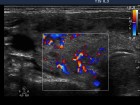

Follow-up examinations (rows from 1st to 8th):

Comments:

1. The patient initially presented with a large thyroid, therefore we suggested definitive therapy.

2. Note the relation between volume, echogenicity, vascularization and hormone levels.